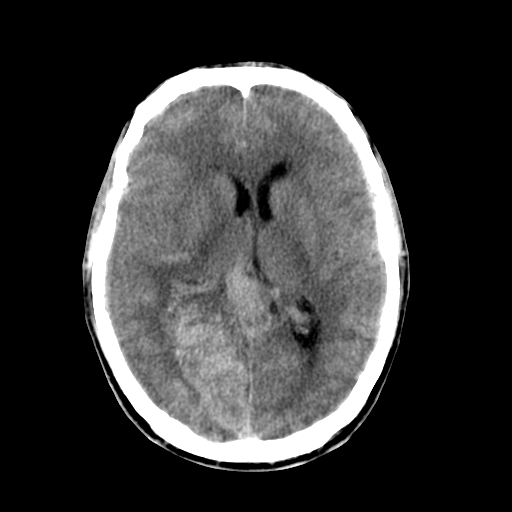

标题: CT17002:M48Y,血管畸形,血管瘤,请鉴赏! [打印本页]

男48y,头痛多年,加重一天!

典型的血管畸形---avm  -----右侧枕顶叶及侧脑室三角区等高混杂密度影夹杂少许低密影显示,无明显水肿,增强可见明显的供血动脉与引流静脉显示